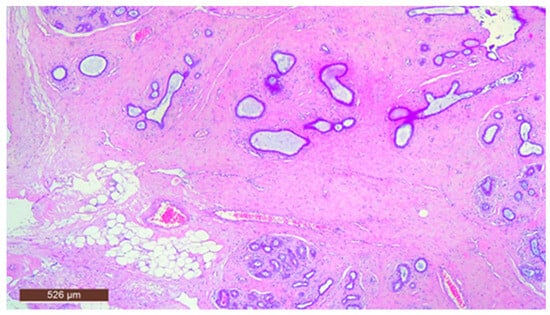

On microscopic examination, a hamartoma may exhibit three predominant components: glandular, fibrous and adipose (Figure 7). Epithelial components such as ducts and lobules are generally normal, featuring a single layer of epithelium overlying the myoepithelial cells. The fibrous component was composed of connective tissue stroma with a delicate connective tissue capsule (Figure 8). Additionally, the ducts within the hamartoma may display apocrine metaplasia (Figure 9).

The stromal component of the lesion is frequently hyalinized and poorly defined, extending around and infiltrating lobular structures, and may exhibit characteristics of pseudoangiomatous stromal hyperplasia (PASH) (Figure 10). Epithelial hyperplasia is uncommon, with only one case of atypical hyperplasia observed in our study.

Figure 9. Ducts with apocrine metaplasia inside a hamartoma (HE ×40).

Figure 10. Hamartoma with pseudoangiomatous stromal hyperplasia (HE ×40).